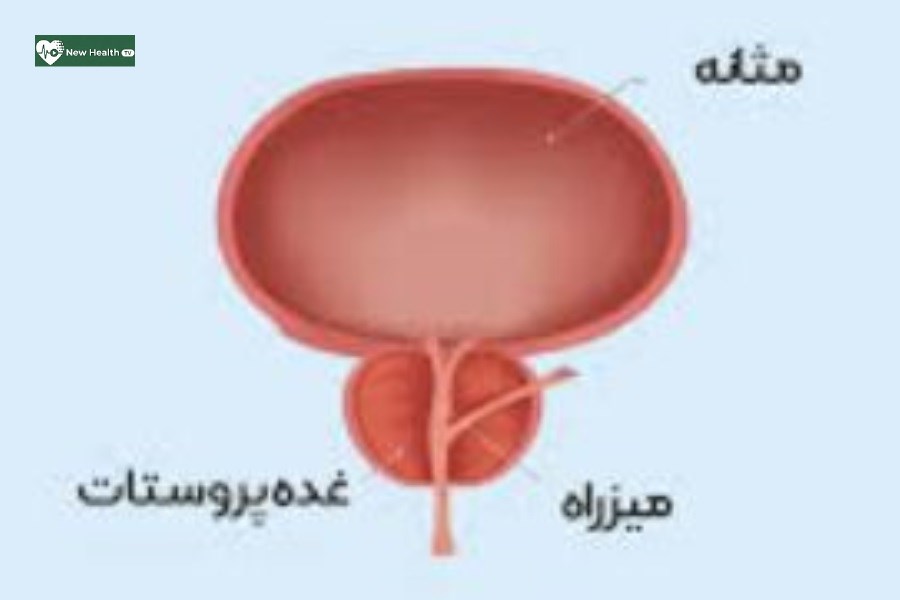

علی ارغوانی متخصص داخلی درباره بیماری پروستات، اظهار کرد: غده پروستات غدهای است که تنها در مردان یافت میشود، این غده در زیر مثانه قرار دارد، سرطان پروستات نوعی بیماری است که در آن سلولهای بدخیم از بافتهای پروستات نشأت میگیرد و به طور نامنظم و فزایندهای تکثیر و منجر به افزایش حجم در هر یک از اجزای سلولی غده پروستات میشوند.